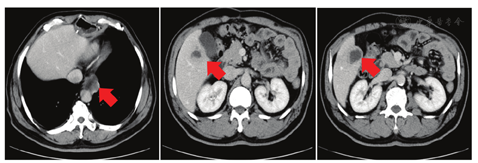

术后ECOG PS评分为1分,因患者拒绝静脉化疗,2018年8月10日至2018年9月21日术后外院行替吉奥60 mg每天早、晚餐后半小时口服,连续口服14 d,每21天为一周期,共化疗2个周期。2018年10月23日复查全身PET-CT示:右侧锁骨上、右侧颈部Ⅳ区、右侧颈部喉返神经旁、降主动脉旁、脾动脉近端近腹腔干多发淋巴结转移,肝S5转移。患者未行治疗。1个月后胸腹盆CT提示降主动脉旁淋巴结转移灶及肝转移灶较前增大(见图1),予紫杉醇脂质体270 mg第1天静脉滴注+顺铂50 mg第1天、40 mg第2~3天静脉滴注,每21天为一周期,共化疗2个周期,2个周期后评价疗效为疾病进展(见图2)。程序性细胞死亡配体1(PD-L1)检测(原手术组织,抗体型号22C3)结果为高表达,肿瘤细胞阳性比例分数(TPS)为80%。2019年2月15日给予帕博利珠单抗注射液200 mg第1天+伊立替康400 mg第2天,每21天为一周期,治疗1个周期。1周后患者出现黄疸,肝功能示:丙氨酸氨基转移酶(ALT)68.6 U/L,总胆红素(TBIL)89.7 μmol/L,直接胆红素(DBIL)83.7 μmol/L。予多烯磷脂酰胆碱注射液等药物治疗后黄疸进一步加重,复查肝功能示:ALT 32.5 U/L,TBIL 235.3 μmol/L,DBIL 215.5 μmol/L;MRI示肝内多发结节部分融合成团,边界不清,肝门部软组织肿物沿胆道系统向肝内蔓延生长,肝内胆管扩张在肝门部截断,胆总管显示不清,考虑转移瘤累及肝门、胆总管。胆囊周围、腹腔及腹膜后、上腔静脉与主动脉间多发结节及肿物,部分融合,大者约6.6 cm×5.1 cm,考虑淋巴结转移。磁共振胰胆管成像(MRCP)示肝内胆管呈"软藤状"扩张,并在肝门部截断,胆总管及胰管显示不清,胆囊显示不清(见图3)。